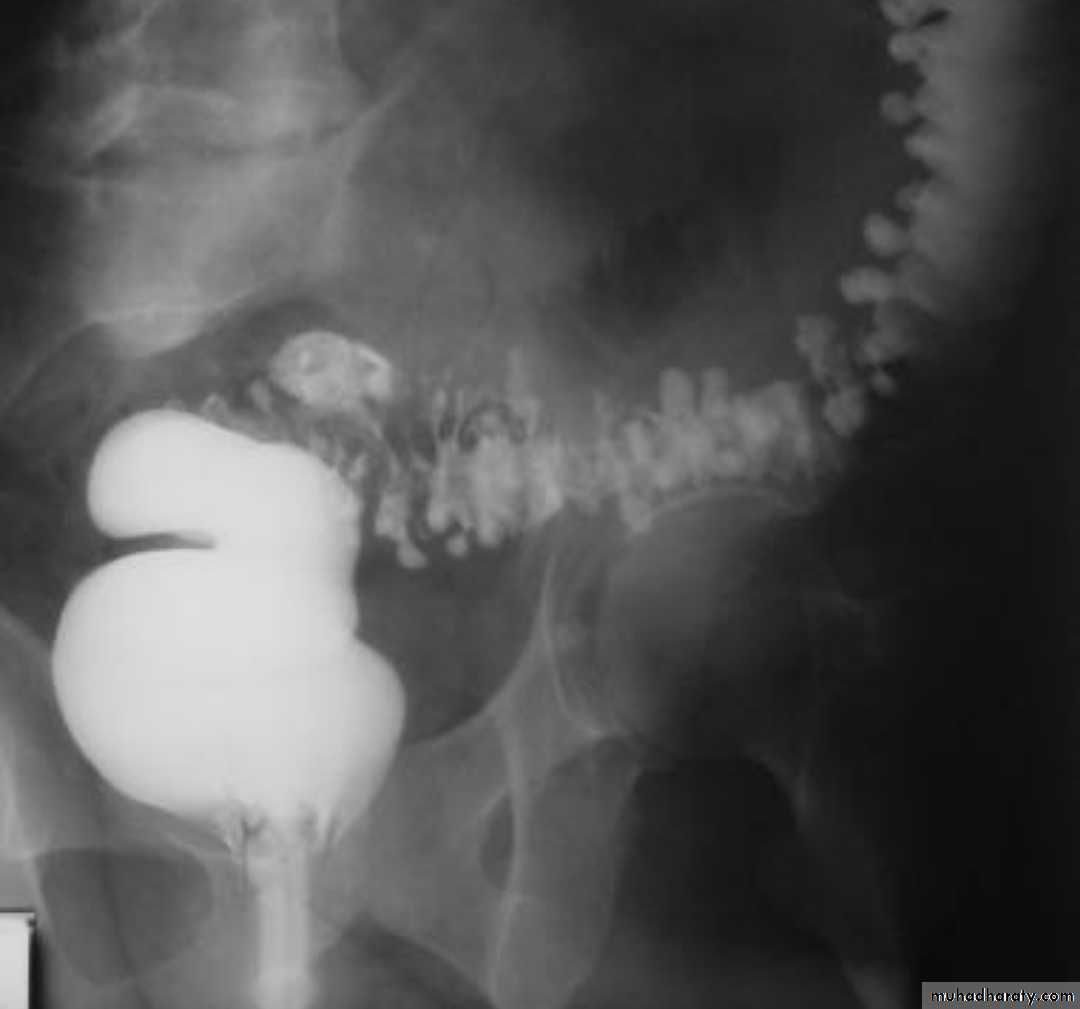

Intussusceptions occurs when one segment of bowel is pulled into itself (or a neighboring loop of bowel) It is an important cause of an acute abdomen in childrenIntussusceptions may also occur in the adult population where it is usually caused by a focal lesion acting as a lead point.

Radiographic features

Intussusceptions can occur essentially anywhere, in children there is a strong predilection for the ileo colic region

contrast enema

A contrast enema remains the gold standard, demonstrating the intussusceptions as an occluding mass prolapsing into the lumen, giving the "coiled spring ” appearance .The main contra-indication for an enema is a perforation

Contrast enema is diagnostic & therapeutic